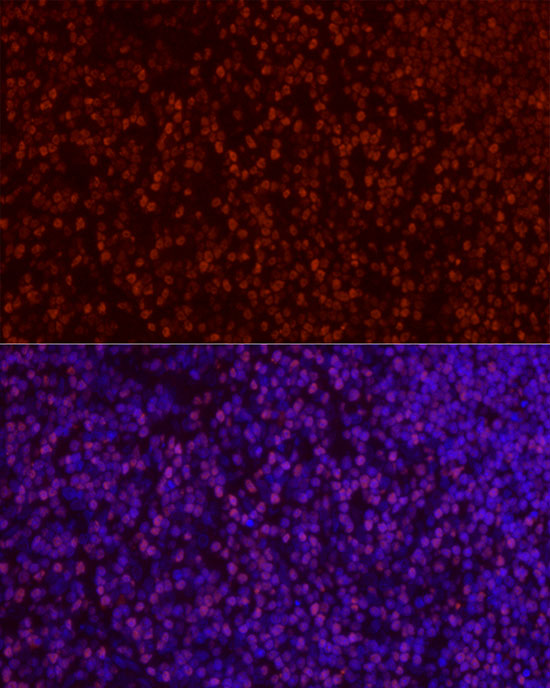

Immunofluorescence analysis of rat thymus cells using SATB1 antibody diluted at 1:100.